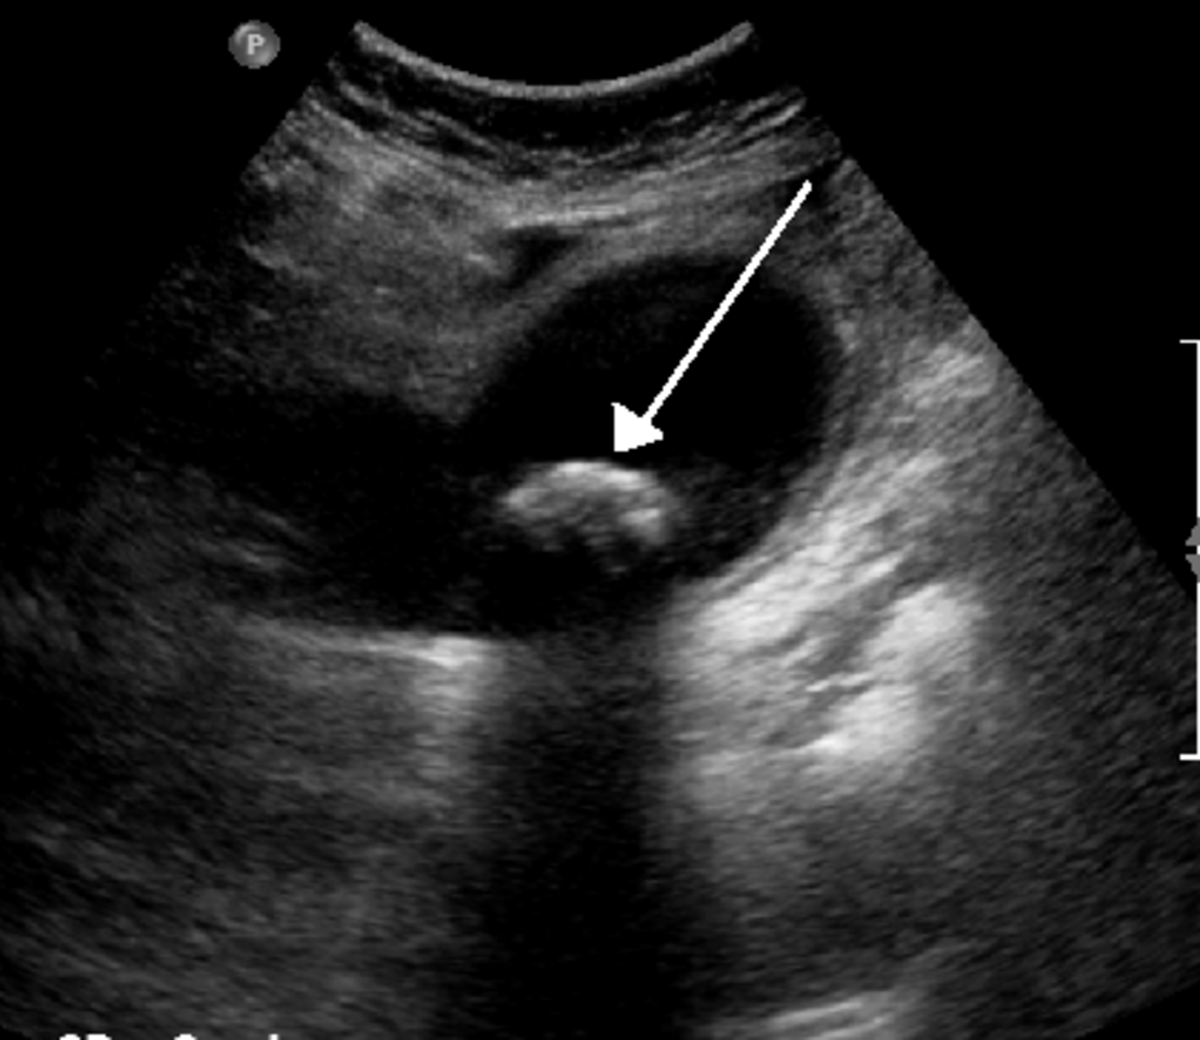

Gallbladder Ultrasound Normal Vs Abnormal Image Appearances Comparison Do Blood Tests Show Gallbladder Problems What tests are used to diagnose gallbladder disease? Blood tests may reveal infection, jaundice, pancreatitis or other complications caused by gallstones. These can check for signs of infection, inflammation, or liver function abnormalities related to gallbladder disease. A blood test may also be performed to help diagnose gallbladder disease. Imaging tests that show your gallbladder. Blood tests can look for. Do Blood Tests Show Gallbladder Problems.